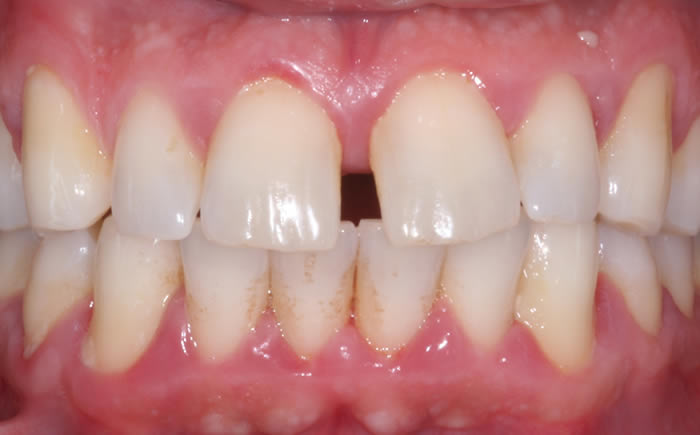

Gum disease

Case Two (2 images)

Treatment of moderate gum disease.